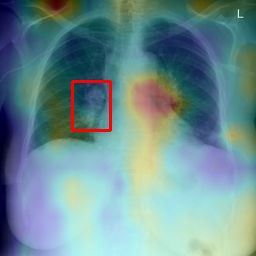

Deployments of artificial intelligence in medical diagnostics mandate not just accuracy and efficacy but also trust, emphasizing the need for explainability in machine decisions. The recent trend in automated medical image diagnostics leans towards the deployment of Transformer-based architectures, credited to their impressive capabilities. Since the self-attention feature of transformers contributes towards identifying crucial regions during the classification process, they enhance the trustability of the methods. However, the complex intricacies of these attention mechanisms may fall short of effectively pinpointing the regions of interest directly influencing AI decisions. Our research endeavors to innovate a unique attention block that underscores the correlation between 'regions' rather than 'pixels'. To address this challenge, we introduce an innovative system grounded in prototype learning, featuring an advanced self-attention mechanism that goes beyond conventional ad-hoc visual explanation techniques by offering comprehensible visual insights. A combined quantitative and qualitative methodological approach was used to demonstrate the effectiveness of the proposed method on the large-scale NIH chest X-ray dataset. Experimental results showed that our proposed method offers a promising direction for explainability, which can lead to the development of more trustable systems, which can facilitate easier and rapid adoption of such technology into routine clinics. The code is available at www.github.com/NUBagcilab/r2r_proto.